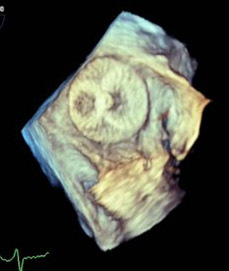

Figure 4. 3D “Top Down” TEE Image of Amulet Device in Left Atrial Appendage |

![]() |

TEE: transesophageal echocardiography |